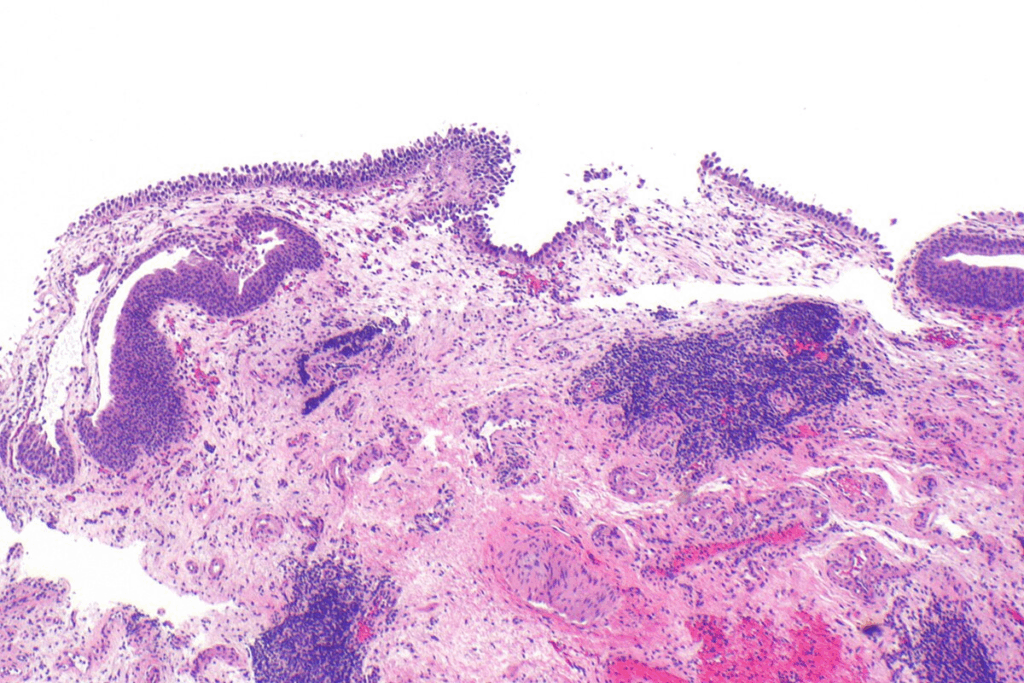

Microscopic Appearance and Identification

Diagnosing carcinoma in situ involves looking at it under a microscope. CIS cells are recognized by their unique features, such as:

- Hyperchromatic Nuclei: Their nuclei are darker because of more DNA.

- Loss of Cellular Polarity: The cells’ normal orientation in the tissue is lost.

- Mitotic Figures: More cells are seen dividing.

Pathologists use these signs to spot carcinoma in situ. They can tell it apart from benign conditions and invasive cancer.